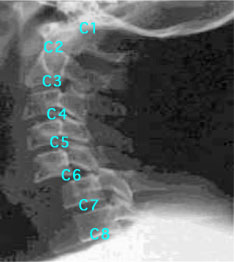

脊髄の中でも首の骨(頸椎)の中を通っている部分を「頸髄」といい、脳に近いほど生命を維持するうえで重要な機能に関わる情報の伝達を担っています。そのため、頸髄の上の部分を損傷するほど、その下の神経が担う部位の機能を失うことになり、一般的に言うと重い障害を負うことになります。ただし、神経組織とは極めて繊細で微少なものなので、脊髄が完全に切れて全く動かなくなる場合(完全麻痺)と、部分的に途切れて所々が動かなくなる場合(不全麻痺)があるように、損傷の位置や度合いによって非常に個人差のある症状が現れます。そのため、障害の大まかなレベルを表すのに、頸髄のどの部位を損傷したかを意味する「C1」(頭に近い部位)〜「C8」(首の付け根)という表記を用います。